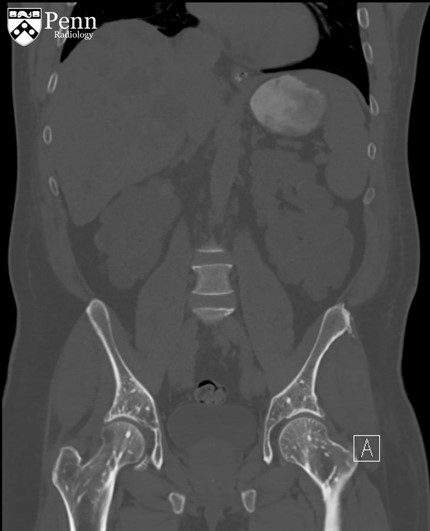

病史 男性,52岁,主诉腹部疼痛伴不明原因菌血症;患者有慢性肾病史。

腹盆CT图像如下

1.CT显示骨密度病变呈不均匀分布?(单选)

2.骨病变有大范围转移?(单选)